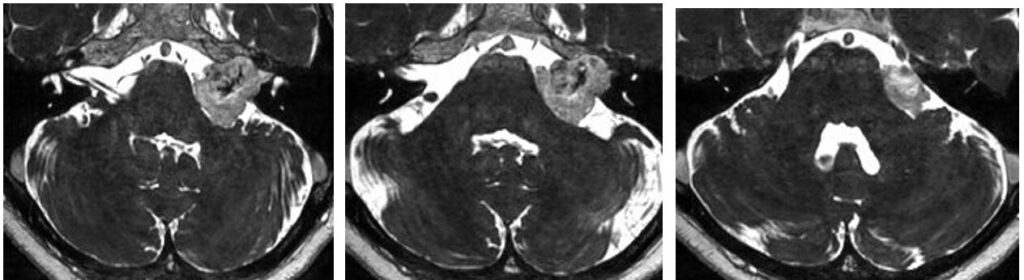

55歳女性、右聴神経腫瘍の手術を行いました。腫瘍は肉眼的に全摘出され、顔面神経麻痺は出ませんでした。